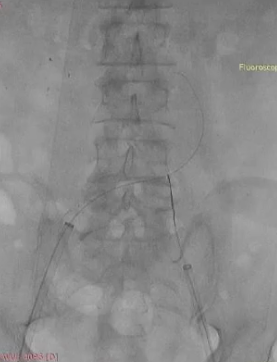

手术过程:根据患者及家属要求保双侧髂内,遂计划双侧髂内重建,右侧优先,左侧髂内情况尝试开通。手术中,先进行造影和翻山建立通路。

造影

翻山建立通路